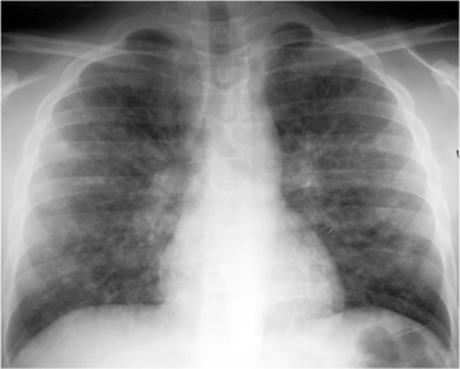

Interstitial pneumonia: This consists of peribronchial thickening and ill-defined reticulonodular opacities (Fig. 5.10). This pattern is typical of Mycoplasma and viruses. Patchy distribution of atelectasis is often seen.

Figure 5.10 Interstitial pneumonia. Bilateral widespread ill-defined opacities.